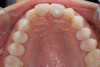

Fig 1. Incisal view (clinical) with impression coping in place demonstrating buccal angulation of implant.

Figure 1